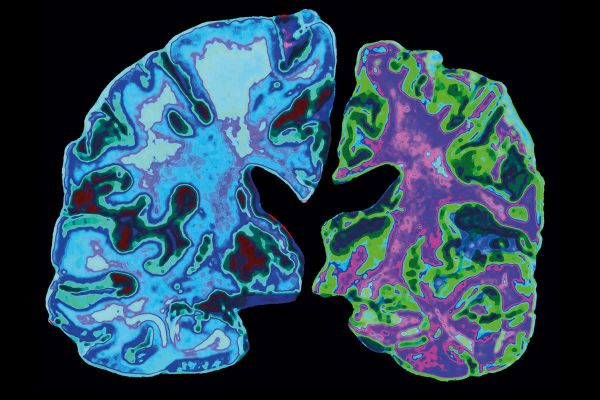

Ευτυχώς ορισμένες κλινικές δοκιμές φαρμάκων που δεν αφορούσαν την COVID-19 συνεχίστηκαν μεσούσης της πανδημίας. Ετσι, την εβδομάδα που πέρασε υπήρξε ένα καλό νέο για τους ασθενείς με νόσο Αλτσάιμερ